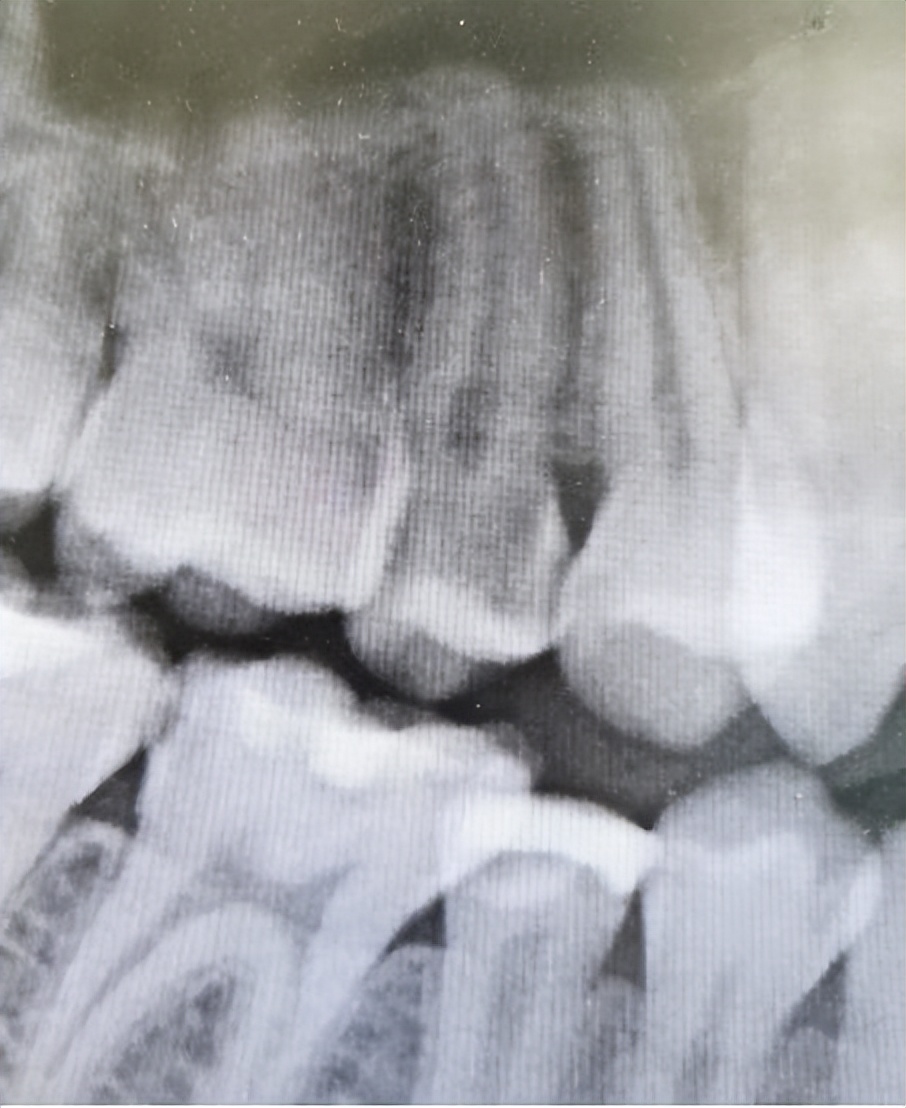

经过系统的口腔检查,我发现患者25牙近中远中邻颌面有深大龋坏,腐质多,检查过程中患者出现痛感,停止操作后,持续疼痛一分钟左右,牙龈缘轻度红肿,对冷刺激敏感。同时X线提示:25牙冠龋坏已经到达髓腔(牙神经)。由于患者对冷刺激敏感,影像学发现牙神经受到炎症波及,有深大龋洞,符合牙髓炎表现,遂诊断为“25牙髓炎”。

因为根管治疗需要利用牙科手机及车针暴露牙髓,继而去除牙齿的龋坏,这个过程可能使牙神经受激,引起较剧烈的疼痛。为了减轻患者疼痛,操作前给予甲哌卡因局部浸润麻醉,然后在根管下打开牙齿髓腔去除龋坏,并完成拔髓,最后给予iRoot sp+热牙胶加压充填,复拍X片恰填后,使用光固化玻璃离子充填,使牙齿冠部暂时封存。并告诉患者1-2周后复诊,进行最后一次桩冠修复。

术前患者25牙近远中及咬合面存在深大龋坏,术后患者腐坏牙体组织去除干净,牙髓炎症感染控制,根管及冠部填充完美,咬合没有出现不适症状,疼痛消失,嘱其避免喝碳酸饮料,少吃甜食,多吃富含维生的的绿色蔬菜,用巴氏刷牙法刷牙,定期来到口腔科复查,随后予以离院。